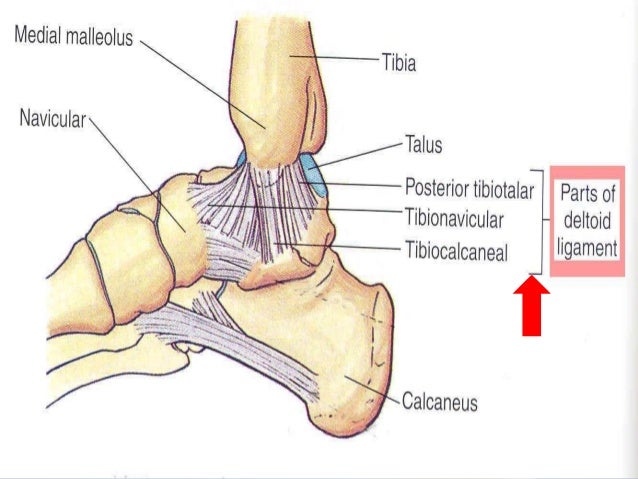

Why an ATFL Rupture does not need surgery. A lot of people panic when they read “ruptured” on a scan or a report. A lot of the time, it’s a cause for concern. In the case of an ATFL rupture, not so much. The ATFL is one of three ligaments making up the lateral ankle complex, along with the PTFL and CFL. The role of the ATFL is to help stop the ankle rolling, particularly when the foot is pointing down.

The anterior talofibular ligament (ATFL) is part of the lateral collateral ligament complex of the ankle. Its role is to stabilize the talus. It is also the weakest of the lateral collateral ankle ligaments.

The three ligaments that compose the lateral complex are the anterior talofibular (ATFL), the calcaneofibular (CFL), and posterior talofibular (PTFL) and they tend to be injured in this order with the anterior talofibular ligament being injured most commonly.

Originating from the fibular malleolus — an area at the end of the calf bone (fibula) — the anterior talofibular ligament connects the talus (ankle) bone to the anterior (front) fibula. It measures 2 millimeters thick, 10-12 millimeters wide, and about 20 millimeters in length. It, along with other ligaments and bones, maintains stability in the ankle joint, protecting it from force.

The Anterior Talo-Fibular Ligament (ATFL) is one of three ligaments that make up to Lateral Collateral Ligament of the ankle. The ATFL is a short ligament that widens slightly from top to bottom.

Where does the anterior talofibular ligament originate?

The anterior talofibular ligament originates from the anterior edge of the lateral malleolus of the fibula and attaches to the neck of the talus, in front of the lateral malleolar facet.